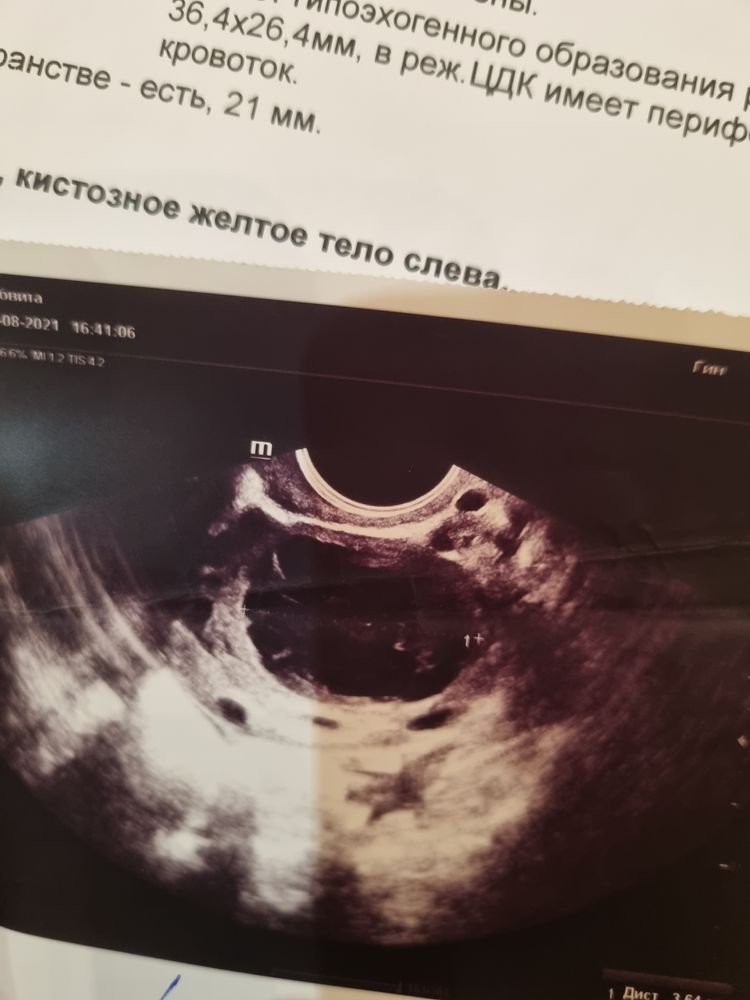

Принимала дюфастон с 16 по 25 дц. Решила сходить на узи фолликулометрию. Т.к после ЗБ, вообще организм себя странно ведёт. И вот такой результат. Фолликулярная киста справа и желтое тело справа, если често не особо понимаю как такое может быть. Сегодня 10 день цикла Т.е возможно, овуляции и не было в этом цикле. Кто сталкивался с подобной ситуацией?

Что такое овуляция- это фолликул, котороый лопнул и из него вышла яйцеклетка. Что такое киста - это фолликул, который не лопнул. Почему вы решили, что это глупость. Росли у вас на одном яичнике 2 доминантных фолликула, один больше, другой поменьше. Во всплеск ЛГ, один лопнул, а второй ещё не был готов, не дозрел. Но т.к всплеск ЛГ происходит 1 раз, меньший доминантный фолликул так и не лопнул , перешёл в кисту. Виола, на одном яичнике киста и жёлтое тело

И желтое тело, и кисту одновременно увидел? Звучит как фантастика (или некомпетентность).

Герда, вот и я удивилась, как такое может быть

Это само узи, вот и гадаю, это киста или желтое тело

Ява, на кисту больше похоже желтого тела, у меня такая же просто похожая была. Советую повторно сходить, что бы по смотрели к другому узисту